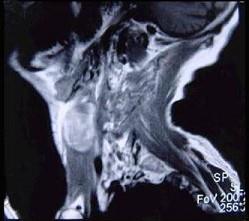

问题 男性,40岁,发现左侧颈部小包块,CT、MRI检查如图所示,请选择最可能的诊断()

选项 A.神经鞘瘤 B.神经纤维瘤 C.海绵状血管瘤 D.肿大淋巴结 E.副神经节瘤

答案 C